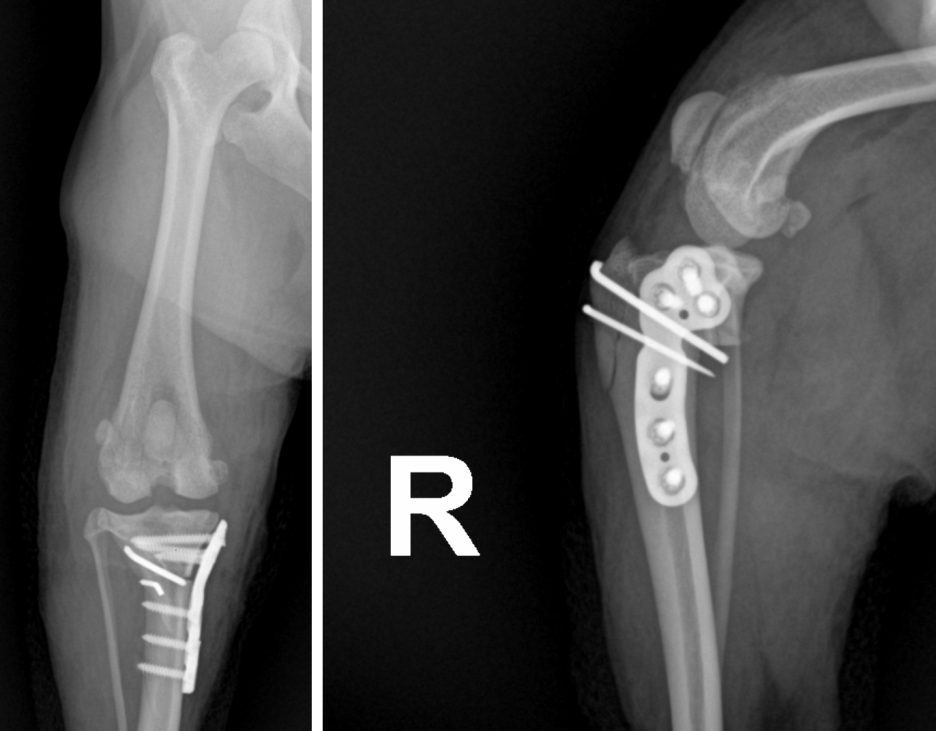

■ 수술 후 경과 (엑스레이 검사)

슬개골 탈구 및 TPLO 수술 후 정상위치로 환납된 슬개골과 TPLO 수술에 사용된 플레이트가 정확히 장착됨을 확인하였습니다.

울산 강아지 TPLO 및 슬개골 수술 후 촬영 사진 / 출처: 에스동물메디컬센터